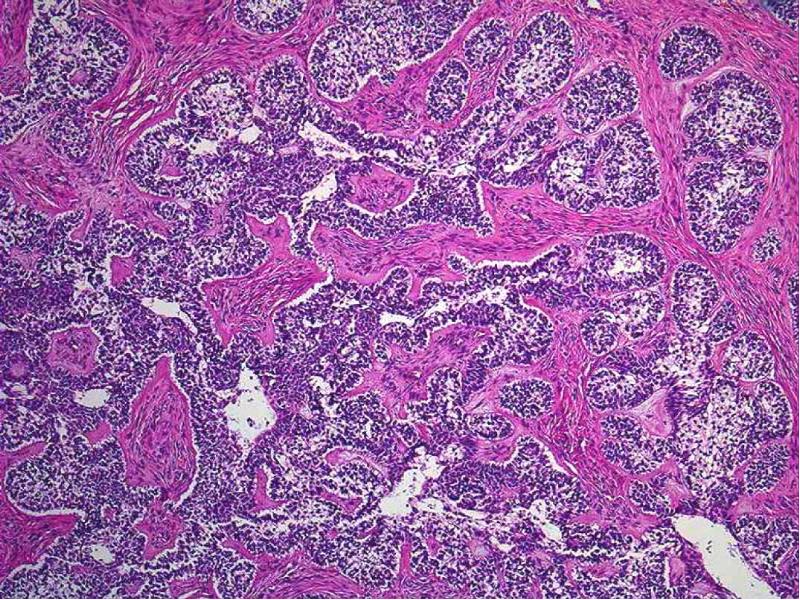

- 14. Микроскопическая картина Гистологически напоминает эмалевый орган Кистозная Фолликулярная Плексиформная Акантоматозная Базально-клеточная